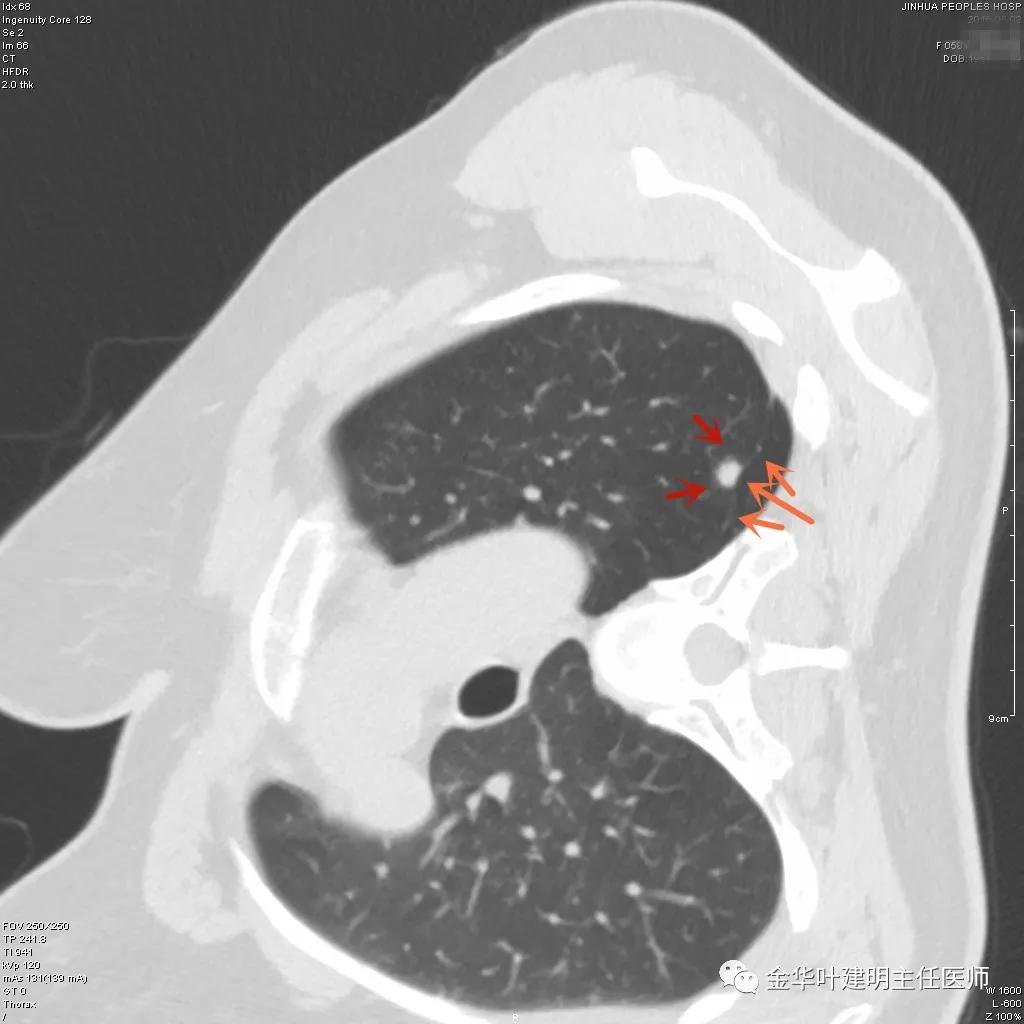

上图示慢性炎结节。我们见其桔色箭头示长毛刺征,绿色箭头示有血管贴边,但进出病灶的血管粗细相对没有什么改变(说明没有被病灶窃取多少血供),整体病灶边缘偏模糊。